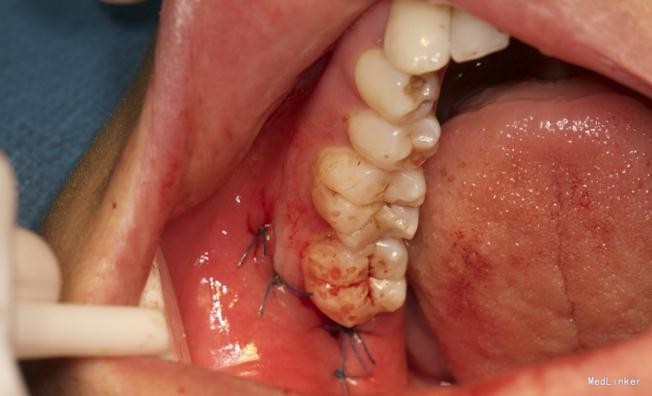

效果很好,患者满意